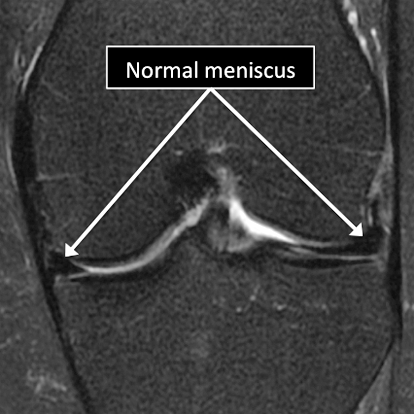

MRI allows us to see many of the different structures in the knee.

Many injuries or diseases affecting those structures can be diagnosed using MRI.

Common things include meniscal tears, ligament tears or degeneration, osteoarthritis, tumors, among many others.

Knee MRI examinations showing normal (top) and abnormal (bottom) meniscus.

Why Translational MRI of the knee?

In the knee, as in many other parts of the body there are certain structures that can’t be seen (they look black or dark) with the standard MRI.

There are new “software” programs that allow us to see structures with different contrast (bright versus dark).

Some of these “invisible” or dark structures are unique to the knee (knee meniscus) and others are found in other parts of the body (e.g. cartilage, tendons, ligaments, cortical bone).

Knee MRI examinations using the standard MRI techniques (top) and translational MRI techniques (bottom).